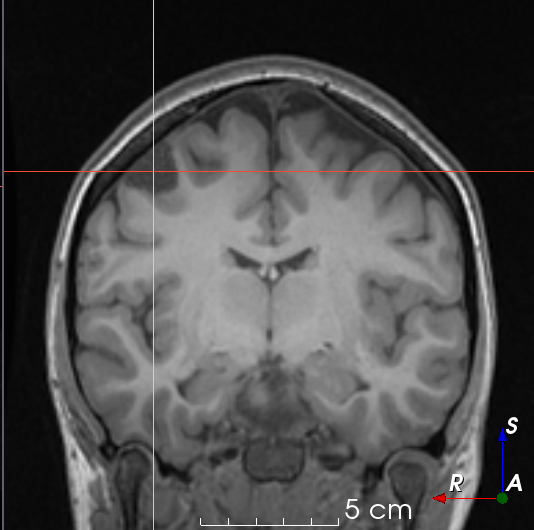

Refer to caption

(a)

(b)

(c)

(d)

(e)

(f)

(g)

(h)

Figure 6: Examples of challenging images for cavity segmentation. (a) Small frontal lesionectomy surrounded by hypointense white matter (b) Brain shift after contralateral temporal lobectomy (not shown) (c) Small frontal lesionectomy near the Sylvian fissure (d) Lack of boundaries between oedema and resection cavity (e) Possible blood clot within the cavity (f) Brain shift, oedema and resection cavity (g) Arachnoid cyst and resection cavity (h) Cerebellar degeneration. Green annotations represent areas that correspond to resection cavities; red annotations represent areas that do not.